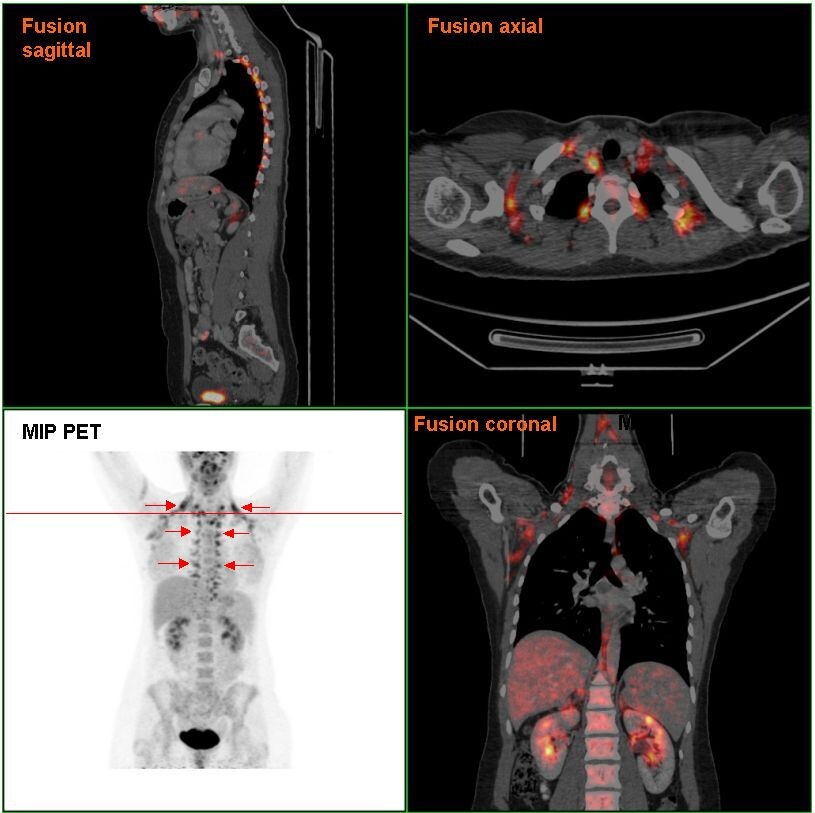

Расположение бурой жировой ткани в организме человека по данным позиционно-эмиссионной томографии. Фото из Википедии.

С помощью современных методов визуализации, таких как позитронно-эмиссионная томография (ПЭТ-КТ), ученые смогли точно определить наличие и активность бурой жировой ткани у взрослых. Эти исследования показали, что активность БЖТ может варьироваться в зависимости от множества факторов, включая возраст, пол и образ жизни. Например, у людей, ведущих активный образ жизни, уровень активности БЖТ может быть значительно выше, чем у тех, кто ведет сидячий образ жизни.